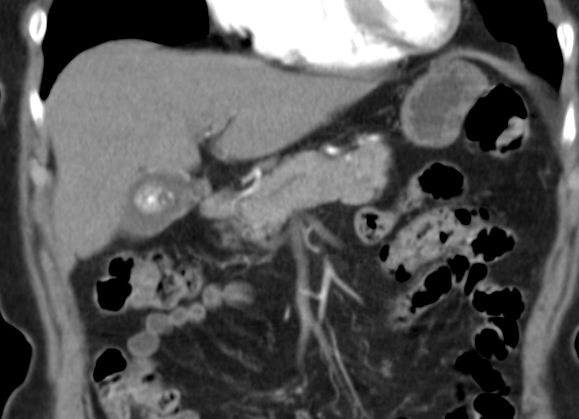

89-jährige Frau mit Infektzeichen. Zunächst sonographisch Verdacht auf Gallenblasenempyem. Im CT ein Gallenblasenkarzinom mit Leberinfiltration. Wegen Alter und AZ palliative Versorgung. | ||